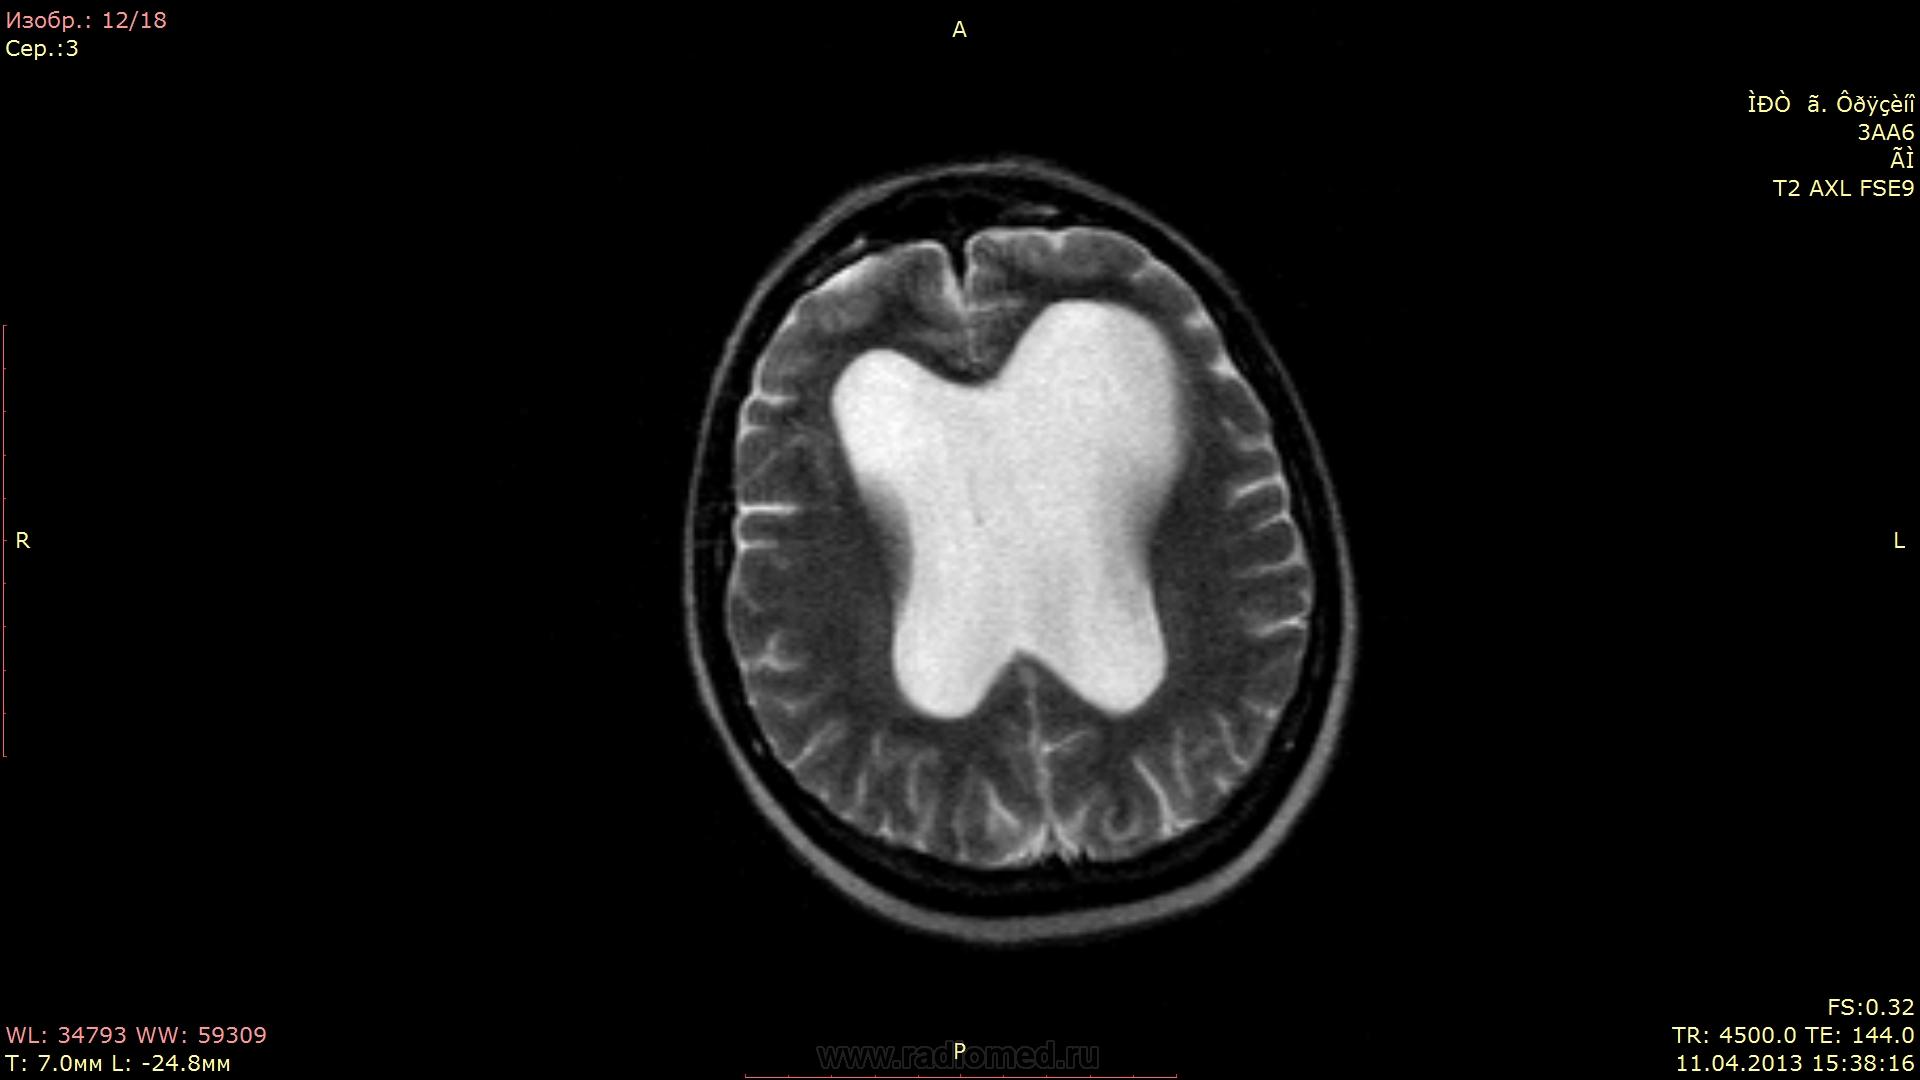

Женщина 53 года... Не могу найти причину гидроцефалии...

Не вижу окклюзии на уровне Сильвиева водопровода. Внутренняя неокклюзионная гидроцефалия.

А вообще-то, от рентгенолога требуется указать на наличие или отсутствие явных признаков повышения внутрижелудочкового давления (перивентрикулярный отек), а в случае наличия такового - выявить уровень и причину окклюзии. Здесь открытая, преимущественно внутренняя гидроцефалия, т.е. окклюзии нет, давление в желудочках условно считается  нормальным, и вмешательства нейрохирурга не требует.

А если рассуждать о причинах - то это, скорее всего, перинатальное гипоксически-ишемическое или травматическое поражение, приводящее к затруднению резорбции ликвора в подпаутинных пространствах. Пациентка живет с этой гидроцефалией всю жизнь.

Там еще и киста прозрачной перегородки, кстати! Не могу подтвердить это литературой, но по моим собственным наблюдениям, у недоношенных детей или у детей с перинатальными проблемами листки прозрачной перегородки часто остаются несращенными.

Давление в желудочках "условно нормальное", но дно третьего желудочка пролабирует в селлярную область:)

Про сочетание вышеописанных признаков достоверно сказать не чего не могу, известно что неврологические проблемы около 2-х лет. В данном случае меня смутила ассиметрия боковых желудочков и пролабирование третьего желудочка, нормальный четвертый желудочек... В общем стаж мой в МРТ очень маленький и я боялся пропустить оклюзию на уровне водопровода.